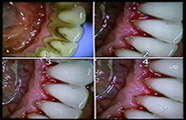

DETARTRAJ DENTAR EFECTUAT IN CABINET DR. PURGHEL TEODOR

Detartraj